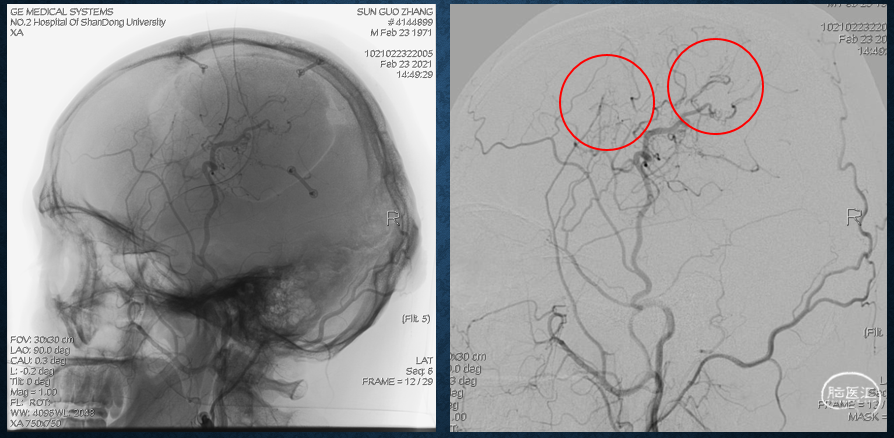

五、 ASL的空间属性—间接血流重建术后新生血管供应范围:

DSA右侧颈总动脉侧位显示右侧颞浅动脉额支、脑膜中动脉后支、枕动脉向脑内少量代偿供血;全脑ASL显示双侧大脑半球血供差。

最终我们选择右侧缺血区,进行两处硬膜翻转筋膜贴敷。

DSA显示颞浅动脉顶支增粗,连同其他新生血管,弥补了大脑半球血供的不足。

ASL显示,右侧大脑半球血供改善,血流来自于右侧颈外动脉。